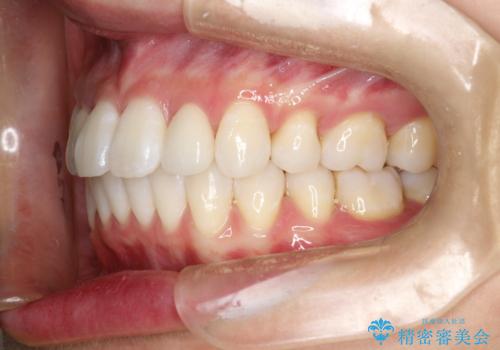

歯の大きさが通常と異なる場合は矯正治療で歯並びだけきれいにしても、整わないことがあります。

その場合はセラミックのかぶせ物を装着して歯の形を正常にすることで、さらに整った歯並びにすることができます。